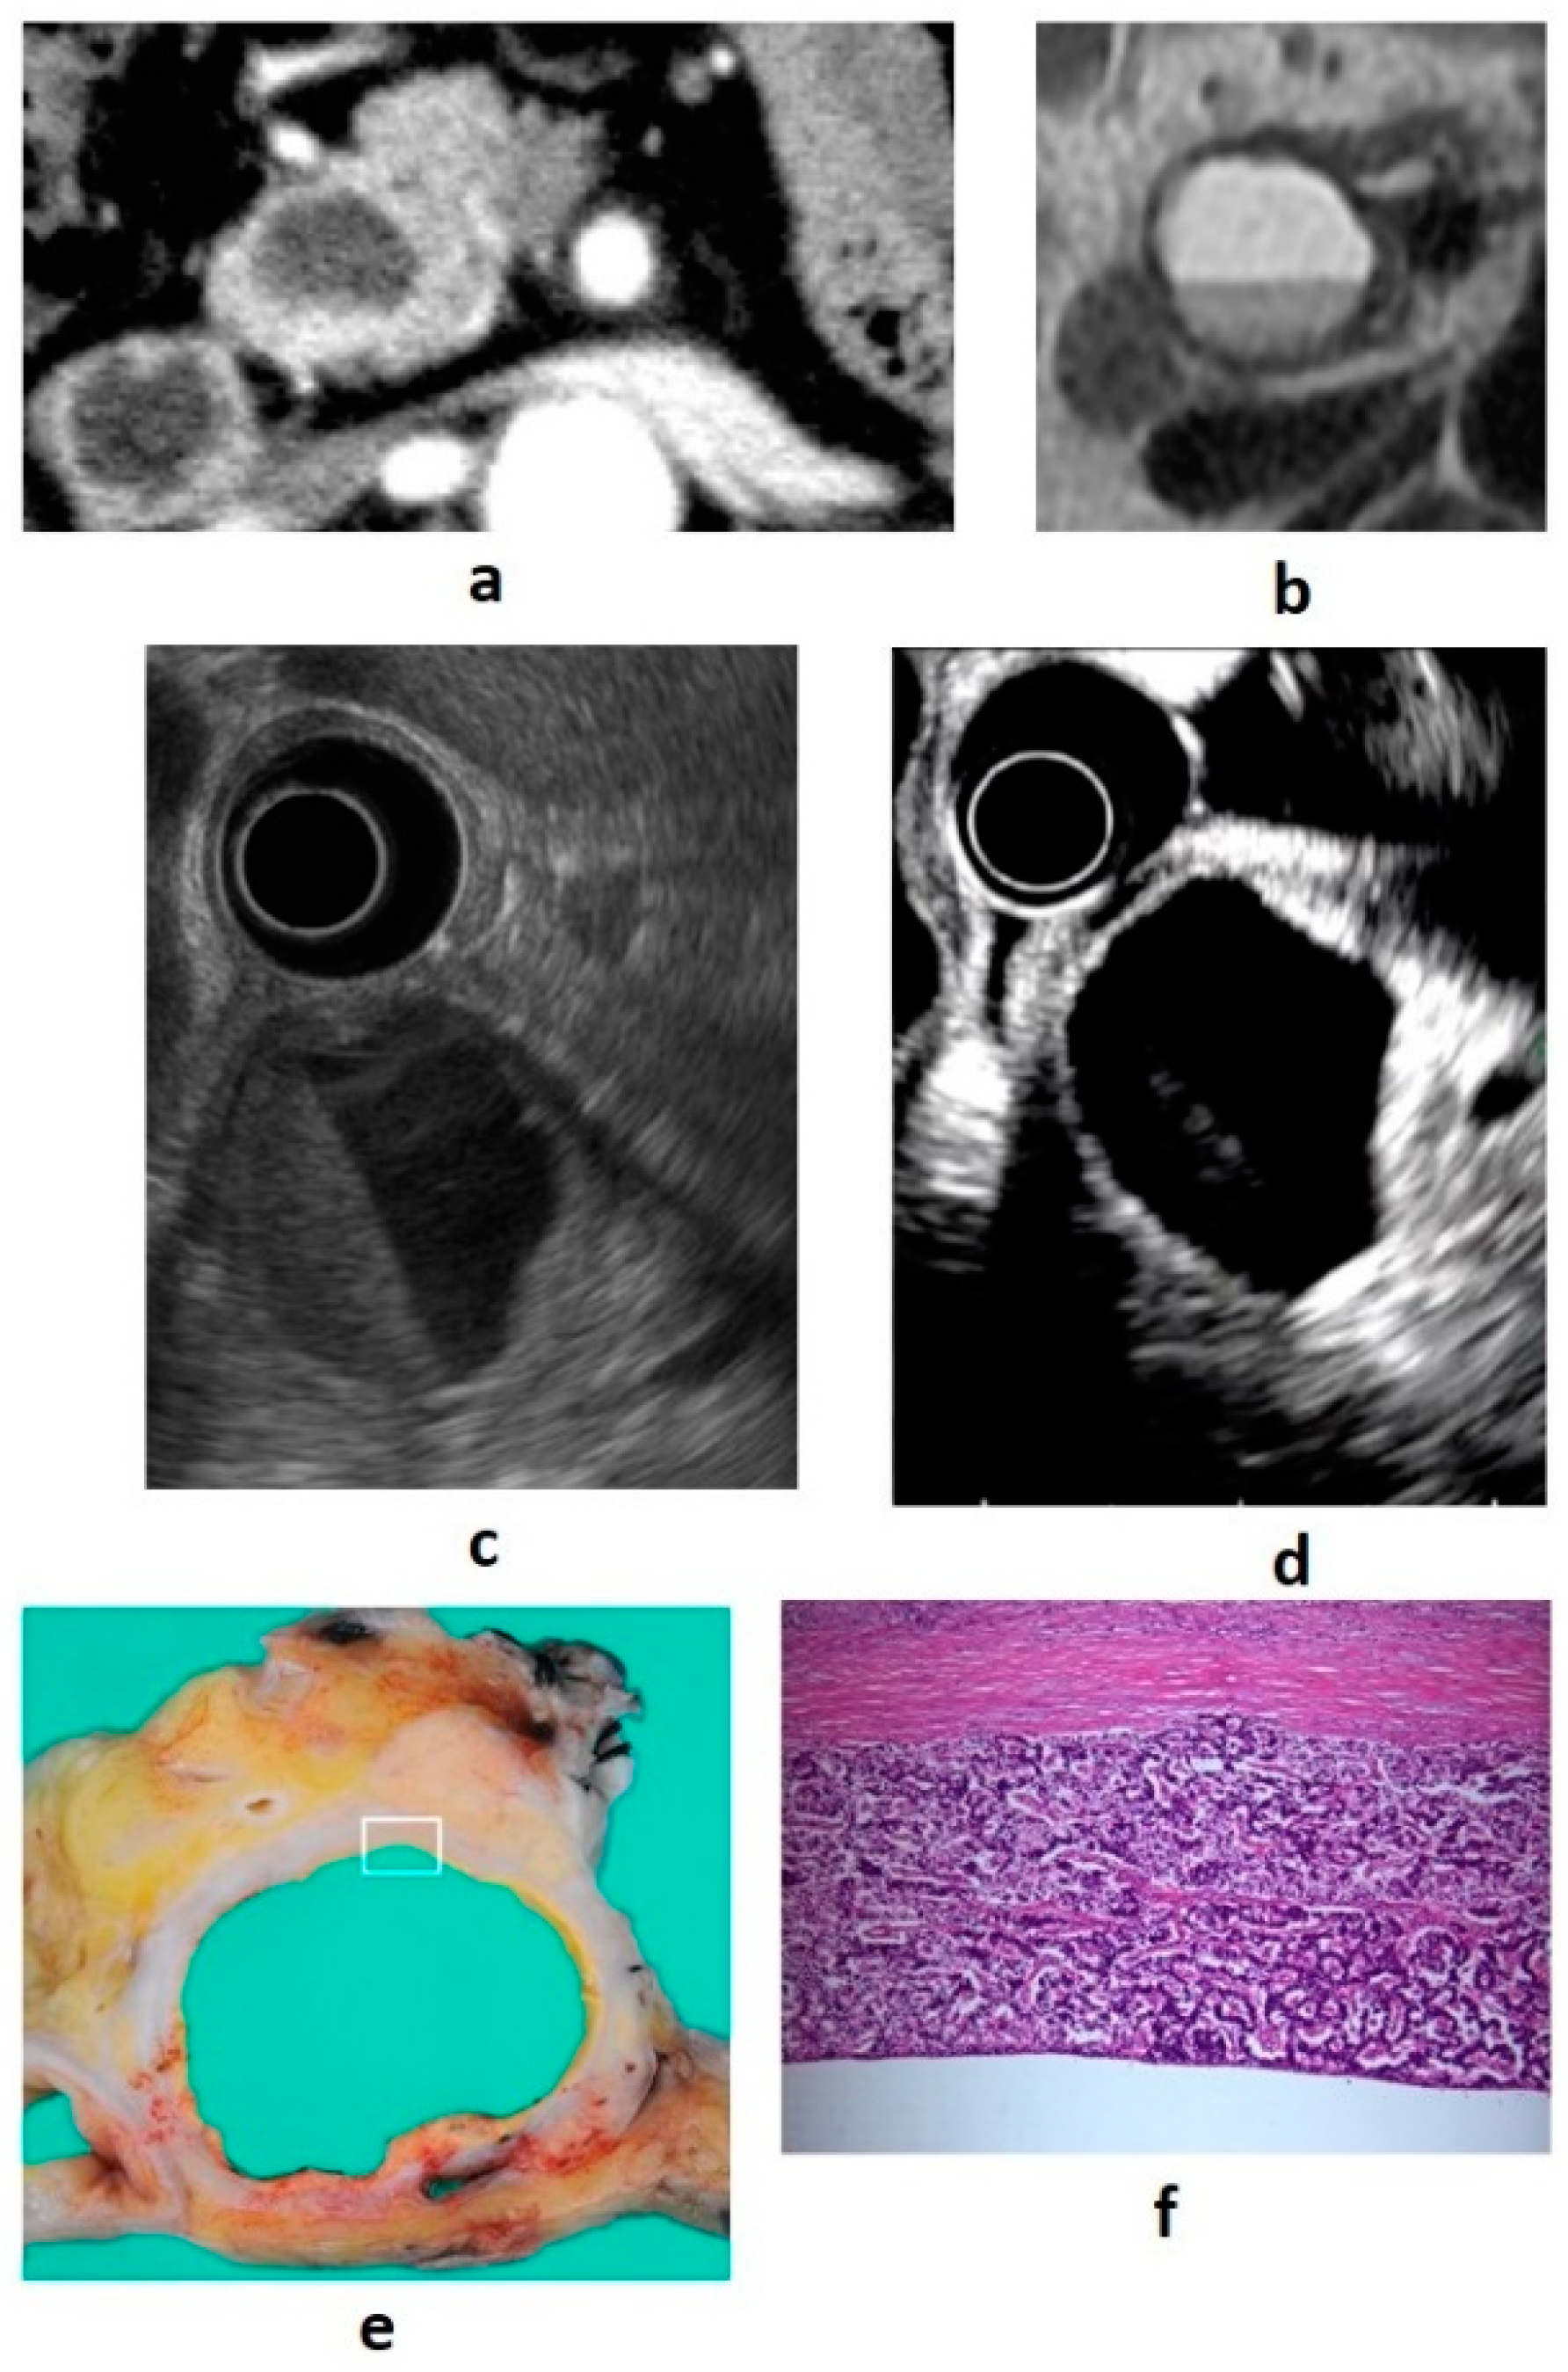

9. Features of Imaging Findings in PNEN G3 and Pancreatic Neuroendocrine Carcinoma (PNEC)

Although there are histopathological differences between PNEN G3 and PNEC, their imaging findings are similar, and both of these tumors show similarities to normal pancreatic cancer (pancreatic ductal carcinoma) and pancreatic acinic cell carcinoma [39]. It has been reported that tumor blood flow correlates with prognostic factors, and the lower the vascularity, the more advanced the malignancy [40]. Histologically, the tumor does not have a capsule and grows invasively. Moreover, the tumor has abundant fibrous stroma, resulting in hypovascularity. The tumor margins are irregular, unclear, hypovascular, and there is internal necrosis of the tumor, and the above-mentioned pancreatic duct stenosis and intraductal extension occur at a high frequency. The necrotic area is recognized as a nonechoic area on B-mode EUS and as an avascular area on CE-EUS. It is difficult to distinguish using diagnostic imaging alone, and pathological examination is required. Examples of PNEN G3 images from our department are shown in Figure 5.

Figure 5. (a) Contrast-enhanced computed tomography (CT): an ill-defined mass (arrow) with a hypovascular enhancement pattern. The dilated pancreatic duct is notable. (b) Endoscopic ultrasound (EUS): irregular margins, unclear boundaries, and heterogeneous hypoechoic masses are shown. (ce) Resected specimen: Ki-67 > 20%, neuroendocrine neoplasm G3 (100×).